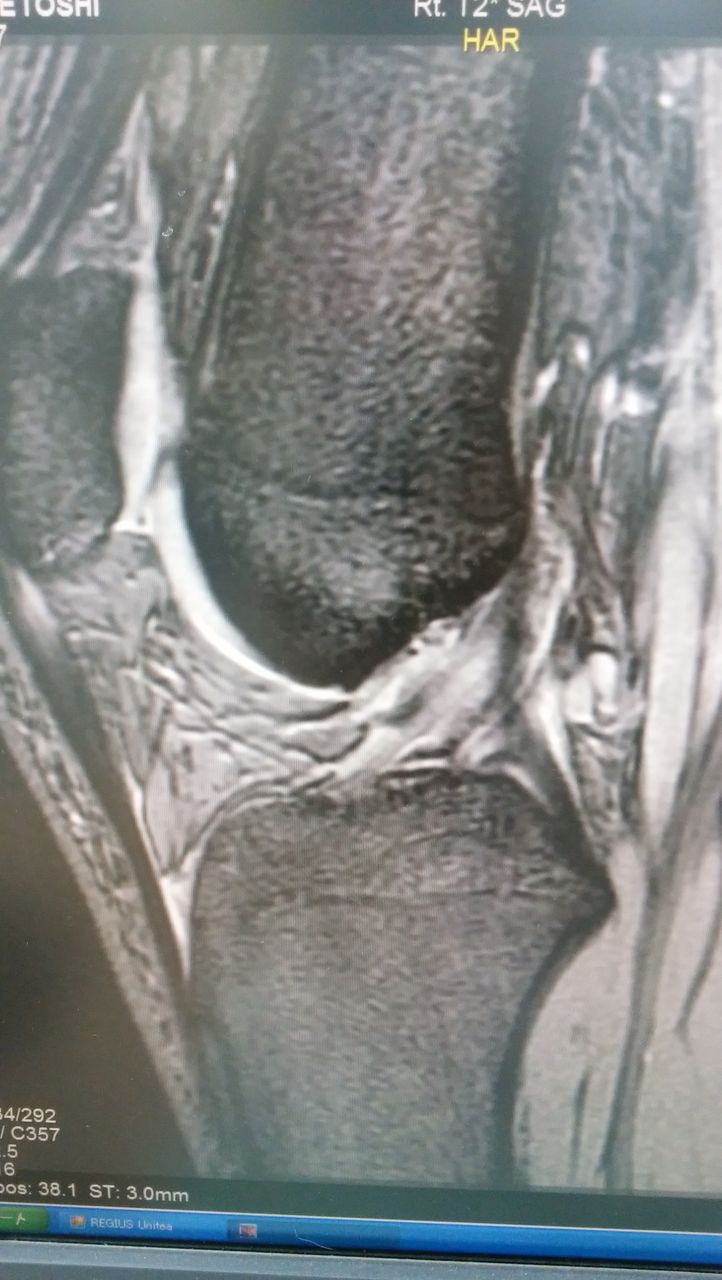

ジャンプの着地に失敗して

前十字靱帯を損傷しました。

今回は千葉から近いこともあり

日本大学病院の膝のプロフェッショナル

森本佑介先生に手術してもらうことに

なりました!